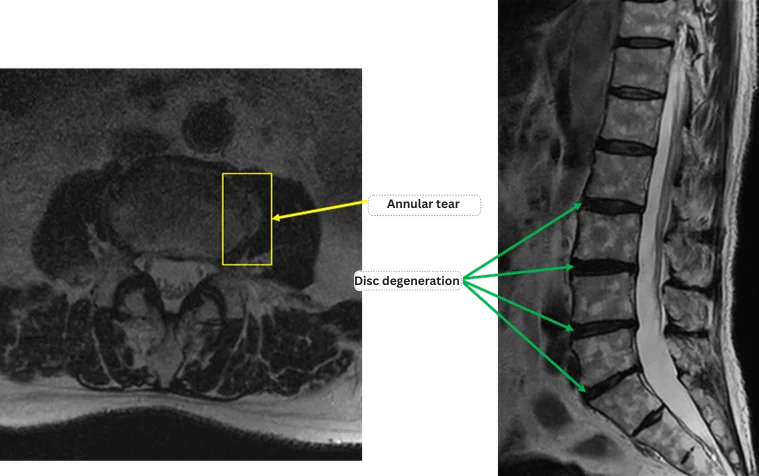

L1/2: Normal.

L2/3: Disc degeneration.

L3/4: Disc degeneration, tear in the annulus fibrosus (annular tear).

L4/5: Disc degeneration.

L5/S: Disc degeneration.

The above findings were also observed on the imaging.

Disc degeneration and annular tear at L2/3, L3/4, L4/5, L5/S are highly suspected to be the primary cause of symptoms.